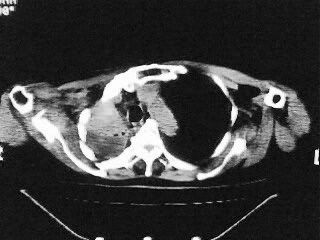

以下是引用随光逐影在2009-2-10 0:07:00的发言:[br]1)右肺放射性肺炎并节段性肺不张?请结合相关病史。2)右侧胸膜肥厚、粘连。3)心包膜增厚(或心包少量积液)。